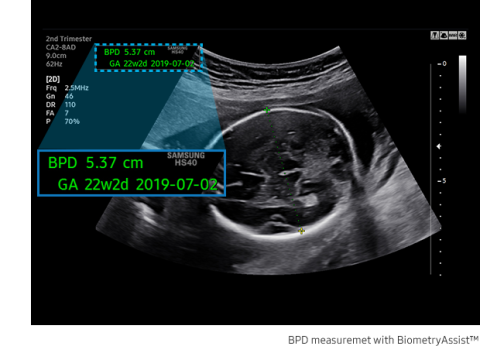

A semi-automatic technology for biometric measurement, BiometryAssist™, enables users to measure the growth of the fetus more quickly and with greater accuracy while maintaining exam consistency.